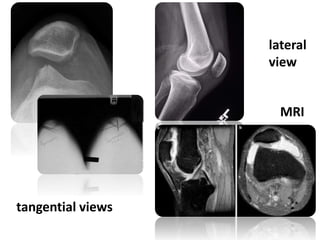

Imaging:

• X-rays

may reveal loose bodies in the knee, derived

from old osteochondral fragments.

 A lateral view with the knee in slight flexion may show a high-riding

patella

 tangential views can be used to measure

the sulcus angle and the congruence angle.

• MRI

helpful and may show signs of the previous patello-femoral soft-tissue

disruption

lateral

view

tangential views

MRI